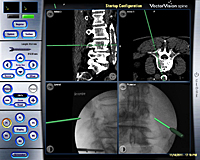

La fijación vertebral consiste en la colocación o implante de tornillos para fijar las vertebras ya sea a nivel cervical, dorsal o lumbar. La utilización de la navegación en este tipo de cirugía, que viene a ser como un GPS, permite realizar dichos implantes con un porcentaje de éxito del 97,6% evitando lesiones del nervio y re-intervenciones por mala posición de los tornillos como puede ocurrir con las técnicas clásicas. Para realizar esta cirugía utilizamos un ordenador y unas cámaras ópticas que permiten, mediante la introducción de las imágenes de una TC preoperatoria y las de unas radiografías realizadas en la posición real quirúrgica del paciente, realizar una fusión de las mismas convirtiéndolas en imágenes 3D reales-virtuales. A través de un instrumental especial, podemos visualizar en directo la trayectoria de los tornillos.